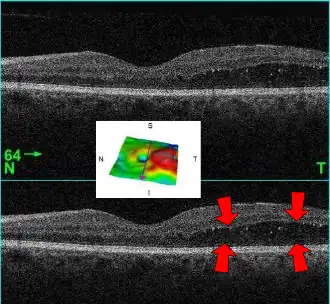

El edema macular es una enfermedad del ojo que consiste en la acumulación de líquido en la zona más sensible de la retina que se llama mácula (un área central y amarilla de la retina).[1]

La retina es la capa más interna del ojo que tiene la propiedad de ser sensible a la luz. La mácula es la porción central y más importante de la retina, es la zona que nos permite distinguir los detalles y reconocer por ejemplo las caras de las personas.

El diagnóstico debe realizarlo el oftalmólogo, que puede distinguir el engrosamiento de la mácula mediante técnicas especializadas; también puede sospecharse mediante la exploración con oftalmoscopio en la que se aprecia una zona de exudados amarillentos que rodean a la mácula, asemejándose a una corona (ver imagen).